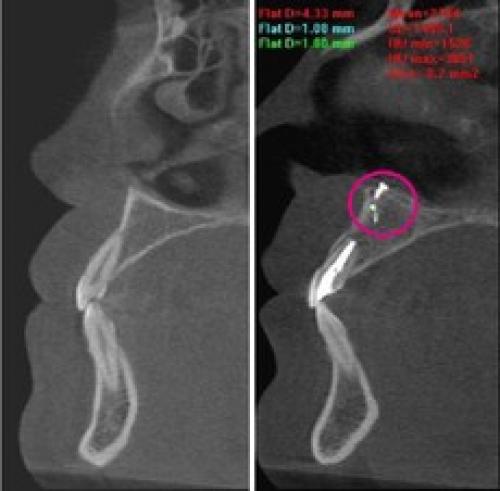

![]() | ![]() | ![]() |

| Выход пломбировочного материала за верхушку зуба вызывал жестокие боли во второй ветви тройничного нерва у мужчины. Вид сбоку:

зуба, кружком обведен | Стреляющая боль во всех трех ветвях была следствием плохого кровообращения в мозговых отделах тройничного нерва у пожилой женщины. Кружком обведен участок мозга, пострадавший от закупорки одного из сосудов головного мозга. Проверить сосуды головы и шеи | Невралгия тройничного нерва была у молодой женщины из-за давления одной из мозговых артерий на корешок тройничного нерва. На МР-томограмме видно пересечение тройничного нерва (идет вертикально) с артерией (идет горизонтально). Артерия оказывала давление на тройничный нерв в месте его выхода из ствола мозга. |